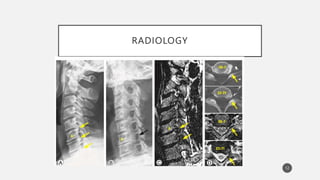

IMAGING

• Xray: AP/Oblique views

• CT:

• MRI:

MRI is considered the imaging method of choice for the

evaluation of cervical radiculopathy.

< 40 years : 10% have disc herniations;

>40 years, 20% have evidence of foraminal stenosis and 8%

had disc protrusion or herniation.

RADIOLOGY